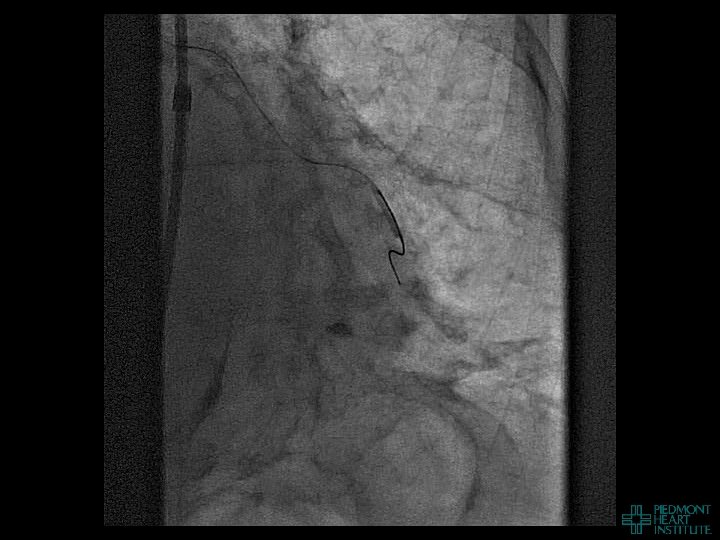

Coronary Perforation Methods of Patient Management • Dual Catheter (‘Ping Pong’) Technique • Prolonged

Coronary Perforation Methods of Patient Management • Dual Catheter (‘Ping Pong’) Technique • Prolonged balloon inflation and covered stents • Reversal of anticoagulation — Know contradictions to protamine sulfate for UFH; Avoid bivalirudin, LMWH — Reserve GP 2 b 3 a inhibition until successful crossing and wire change-out Embolization • — Coil, gelfoam, methacrylate, autologous blood/fat • Microcatheter Occlusion • Confirmation of successful management — Contralateral injection — Right heart catheterization — Echocardiogram — Contrast echocardiography